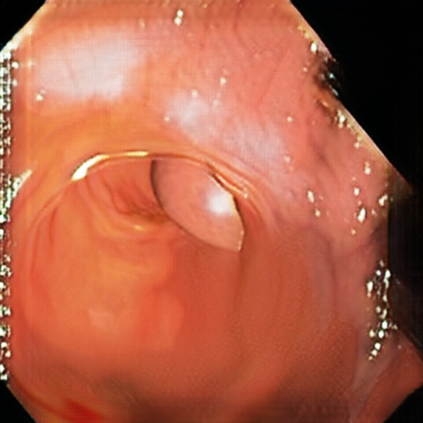

Deep learning has shown excellent performance in analysing medical images. However, datasets are difficult to obtain due privacy issues, standardization problems, and lack of annotations. We address these problems by producing realistic synthetic images using a combination of 3D technologies and generative adversarial networks. We use zero annotations from medical professionals in our pipeline. Our fully unsupervised method achieves promising results on five real polyp segmentation datasets. As a part of this study we release Synth-Colon, an entirely synthetic dataset that includes 20000 realistic colon images and additional details about depth and 3D geometry: https://enric1994.github.io/synth-colon